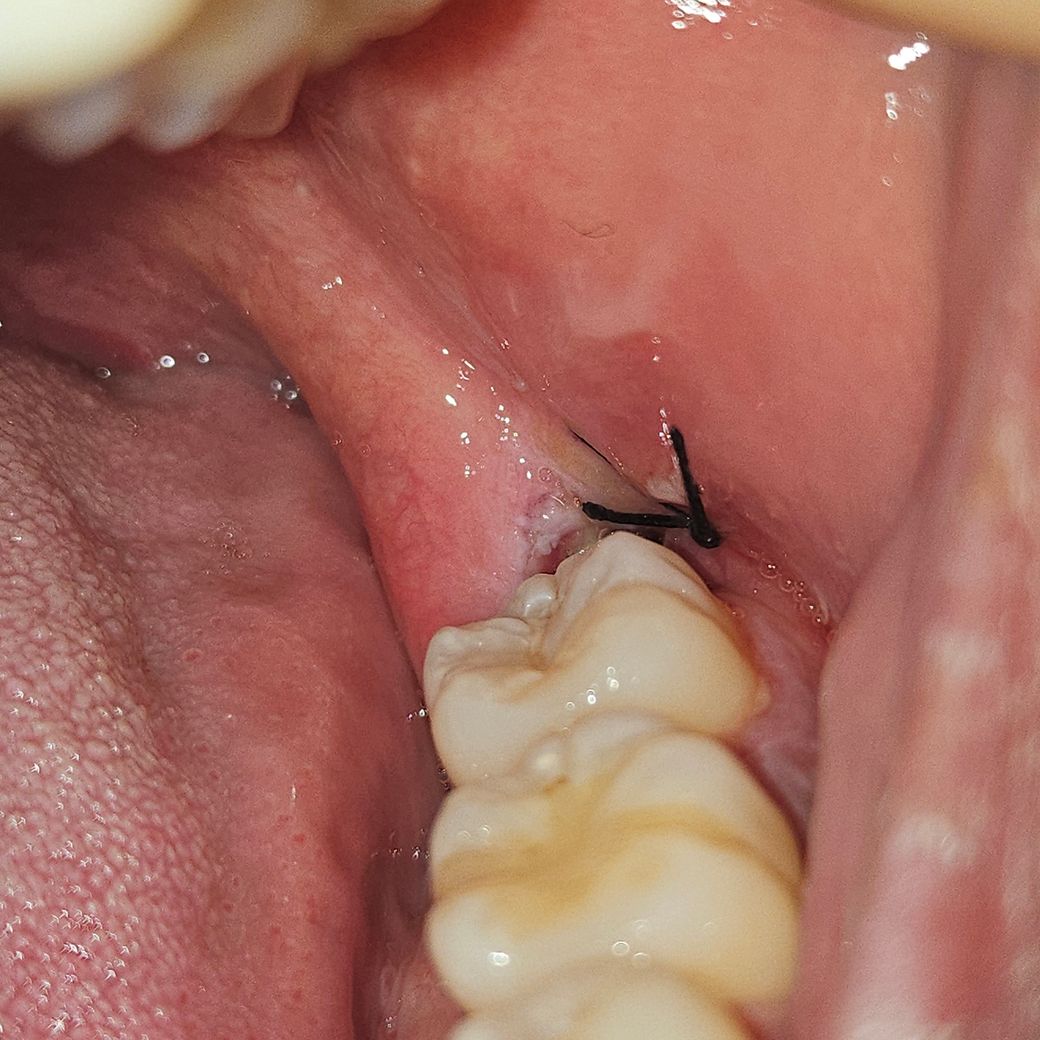

사랑니 발치 30시간째인데 이거 잘 아물고 있는건가요?

안녕하세요 사랑니 발치한지 30시간 조금 넘었는데 가만있으면 입에 피맛이 좀 돌아요 찾아보니까 혈병이 생기려면 진한 빨간색인거 같던데 저는 전혀 아니어서 잘 낫고 있는건지 궁금해요

• 1번 째 사진

사진상으로 보면 크게 문제가 잇는건 아닌거 같습니다. 실밥을 푸실때까지 음식물만 끼지 않도록 해주세요.

현재 사진상으로는 염증 등의 소견은 전혀 보이지 않습니다. 걱정하지 않으셔도 될 것 같습니다.

사진으로만 봤을경우 잇몸은 잘 아물고 있는것으로 보입니다.

사랑니 발치 후 30시간이 지난 상황에서 피맛이 나는 것은정상이며, 현재 잘아물고 있는 것으로 보입니다. 하지만통증 및 붓기가 있는 경우에는 치과에 방문하여 상태를 확인해보길 권합니다.